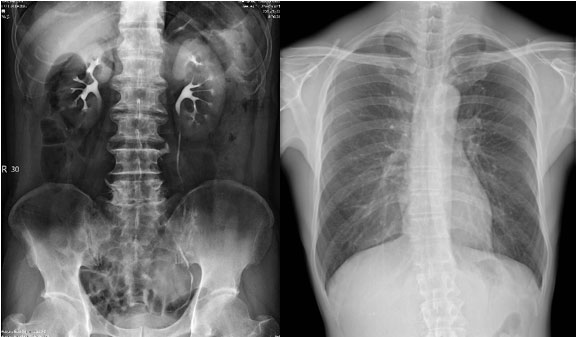

多种临床应用选择

SONIALVISION C200配置多种高级临床功能:可拓展设备的使用范围,完成多种特殊检测需求。